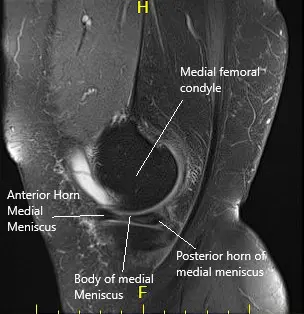

MRI of the left knee suggested a complex tear of the body and posterior horn the medial meniscus. Moderate patellofemoral chondromalacia associated moderate-sized joint effusion and capsular inflammation.

MRI of the left knee in sagittal and coronal sections.